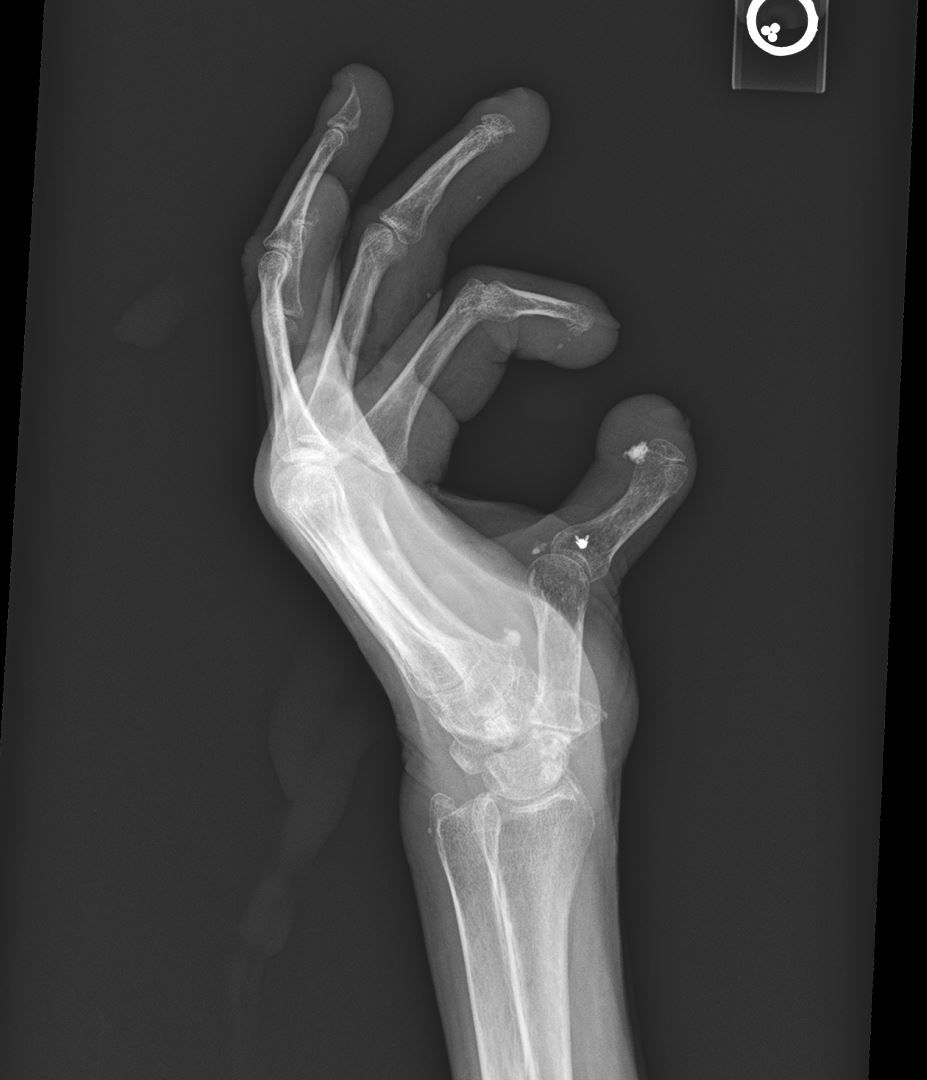

An elderly woman presents with worsening hand pain. What is the most likely diagnosis?